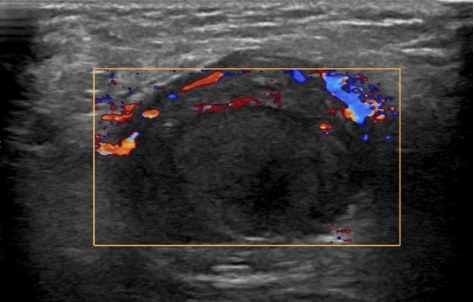

Doppler-echo van een lies.

Een 6-jarige jongen met een blanco voorgeschiedenis kwam op de Spoedeisende Hulp met een toenemend pijnlijke zwelling in de rechter lies sinds 4 dagen. In de rechter liesregio was een zwelling van 7 cm zichtbaar. Rechts in het scrotum was een structuur te palperen, die niet duidelijk als testis herkenbaar was. Er wordt een Doppler-echo verricht.